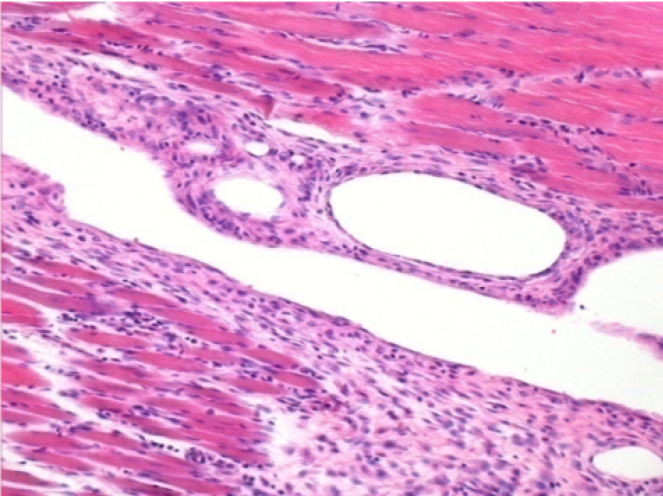

Через 1 місяць після ін'єкції Ендопілу 0,1 мл у правий претибіальний м'яз.

Те, що видно на знімках чорним кольором, не є некрозом, як можуть собі уявити деякі науковці!

Насправді, слід взяти до уваги 4 висновки